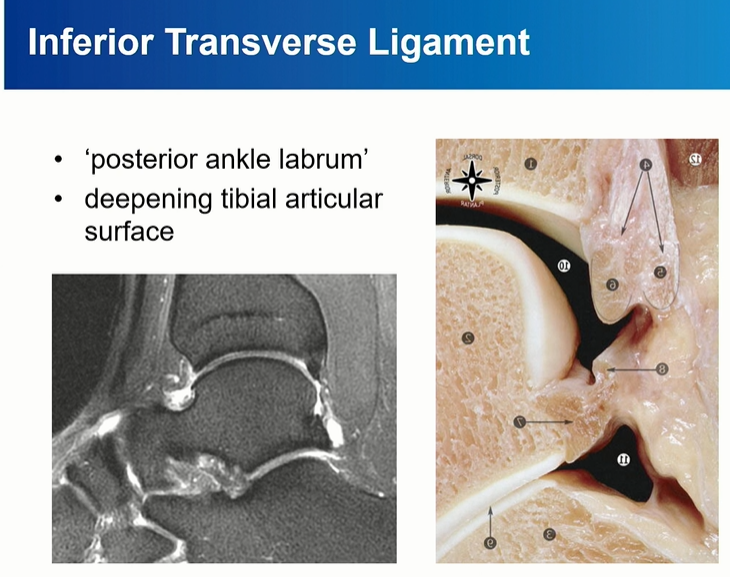

deep component를 inferior transverse ligament라고 부름. 이름대로 horizontal 하게 주행하는 것을 확인할 수 있다.

Deep PITFL인 interior transverse ligament는 labrum으로 역할을 한다. 관절면을 deepening 해줌.